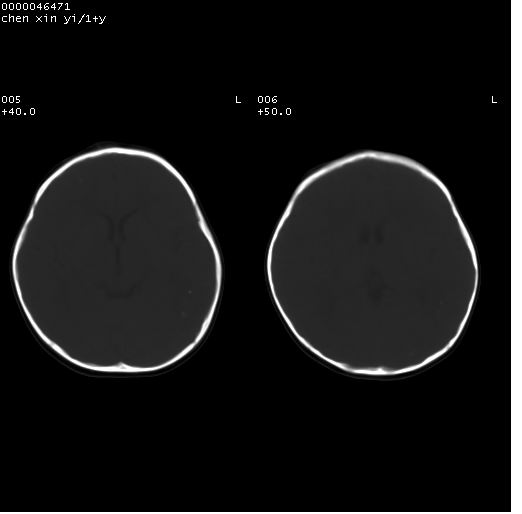

以下是引用zhangzhongshou在2008-4-9 12:54:00的发言:[br]请结合病史,有以下可能1、炎性肉芽肿钙化(含结核)2、寄生虫钙化(含脑囊虫)3、其他良性钙化性病变